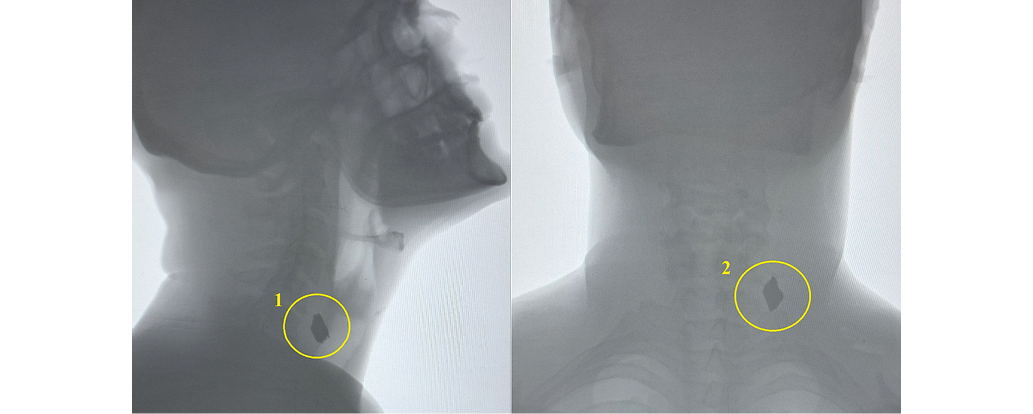

Neck radiography revealed a metallic foreign body (fragment) measuring 2x2 cm within the deep tissues of the left neck (Fig. 2).

Images obtained by the authors

Fig. 2. Neck radiography: 1 — lateral neck radiography: metallic foreign body (fragment) in the left neck tissues; 2 — anteroposterior neck radiography: metallic foreign body (fragment) in the left neck tissues